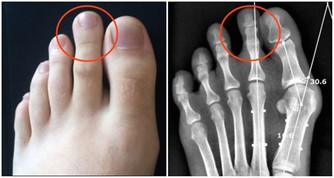

關節僵硬:它們最怕5個字

關節是骨骼之間的連接點,一旦關節出了問題,人的行動力就會受限,久之人就垮了。

1、怕老:隨著年齡的增長,人體軟骨營養缺乏,骨骼中的無機物增多,骨骼彈力與韌性減低,易導致關節軟骨和骨退行性病變。

2、怕胖:體重增加,下肢關節承重的壓力也會增加,引起體位、步態變化,改變關節的生物力學,發生膝內翻或膝外翻,也就是常說的“O”形腿或“X”形腿。